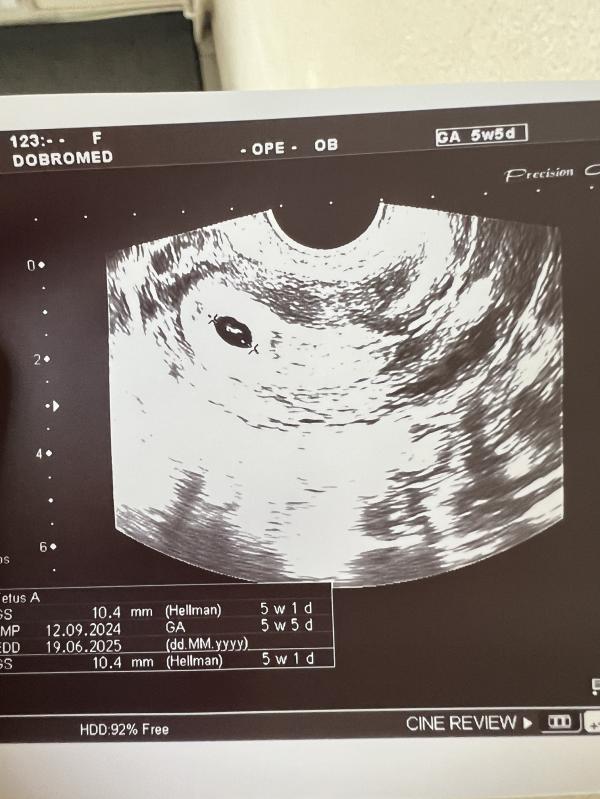

Когда услышим сердцебиение малыша?

Ура, растем ❤️ через недельку услышим сердечко ❤️